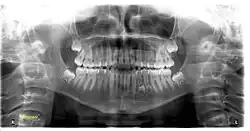

Tooth regeneration is a stem cell based regenerative medicine procedure in the field of tissue engineering and stem cell biology to replace damaged or lost teeth by regrowing them from autologous stem cells.[1]